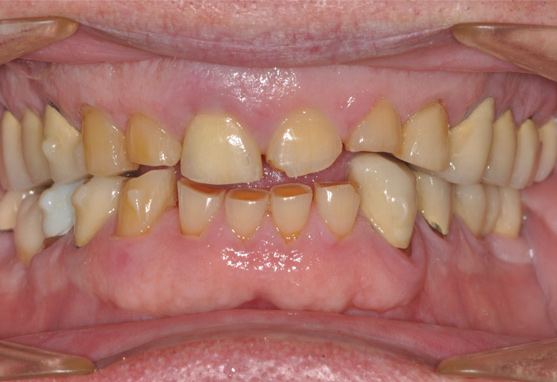

A 76-year-old, retired businessman presented to the office to improve his smile and overall oral health (Figure 1). An esthetic assessment revealed minimal display of the upper anterior teeth and dark discoloration of all teeth (Figure 2). Cephalometric analysis determined that the ANB measurement was 4°, indicating a mild Class II skeletal pattern with upright and retroclined incisors. At 145°, the interincisal angle was excessive, and at 6°, the 1-NA measurement was less than ideal (ie, 22°). If the root angulation of the upper incisors could be shifted toward the palate, it would improve the display and function of the upper anterior teeth with less restrictive anterior guidance (Figure 3).

A more comprehensive examination determined that the patient's anterior teeth bite in an end-to-end relationship with a wide area of contact, which resulted in moderate to locally severe anterior dental wear. Possible crossover bruxing with a flat lower incisor wear table was noted. In the absence of orthodontics, supraeruption of the worn teeth contributes to a poor prognosis for conservative restoration without crown lengthening and gingival reduction. Additional findings included an undersized mesial-distal width of the upper and lower anterior teeth with reduction in the dental arch perimeter; missing teeth Nos. 19 and 30 with distal drift of Nos. 20 and 21, leaving space distal of No. 22; a fixed bridge restoration for tooth No. 19 and an implant fixture in the tooth No. 30 site, both requiring repair; and some concern regarding inadequate oral hygiene.

(2.) Pre-treatment anterior bite.

Image 2